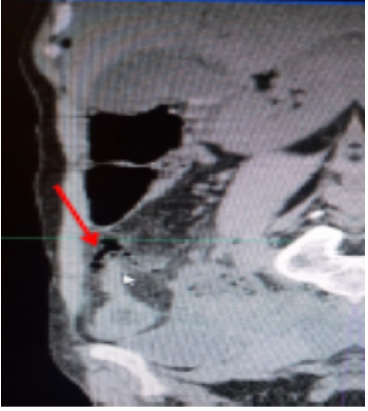

A body computed tomography was performed, revealing circumferential parietal thickening of the last ileal loop, measuring 10 mm and extending over 30 cm, with arterial enhancement and parietal loss of substance of an ileal loop estimated at 02 cm in extent, located 10 cm from the ileo-caecal junction, with multiple air bubbles and fluid opposite. This was associated with infiltration of mesenteric fat. The imager concluded that the peritonitis was due to perforation of the last ileal loop in Crohn's disease (figures 1 and 2).

Figure 2.Computed tomography (coronal section) showing extra-digestive air bubbles (red arraow) opposite the last ileal loop which is thickened